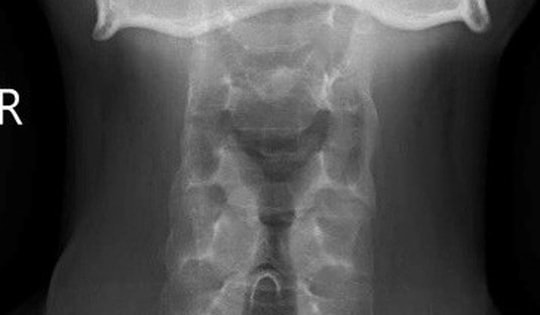

Đau cột sống cổ âm ỉ 5 tháng, nam thanh niên 26 tuổi phát hiện viêm cột sống dính khớp

Một nam thanh niên 26 tuổi, là nhân viên văn phòng, vừa được chẩn đoán viêm cột sống dính khớp thể trục tại Bệnh viện E sau nhiều tháng điều trị không hiệu quả do chẩn đoán ban đầu chưa chính xác.